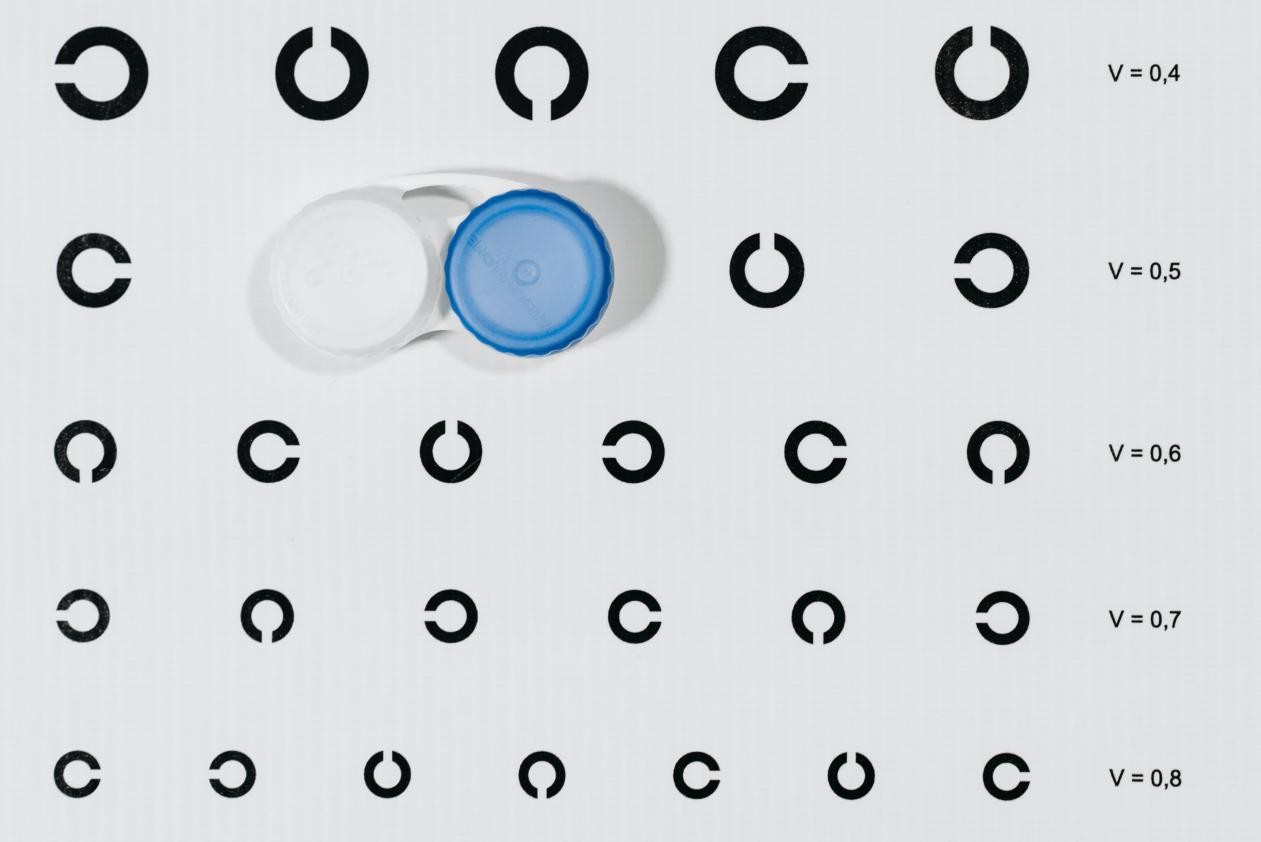

硬性透氧性角膜接触镜,缩写为RGP(RGP即Rigid Gas Permeable Contact Lens的英文缩写)。RGP所含的硅、氟等聚合物,能够大大增加氧气的通过量。与软性隐形眼镜相比,既提高了透氧性,又保证材料的牢固性,并且具有良好的湿润性和抗沉淀性。它对青少年真性近视和圆锥角膜的控制、矫正治疗效果经受了国内外眼科专家多年的临床验证。

RGP与软性隐形的区别?

软镜

材质:含水高分子化合物。

特点:验配较简单,配戴方便且相对舒适。

缺点:透氧性差,配戴不当容易发生结膜炎、角膜炎等并发症,更换周期较短。

RGP

材质:质地矫硬的疏水材料。

特点:透氧性强,抗蛋白沉淀、护理方便,光线成像质量佳,泪液镜矫正散光效果好,适合圆锥角膜、不规则角膜等,更换周期更长。

缺点:验配较复杂且需要一定的适应期。

RGP适合哪些人?

▲RGP的适应度数为正负(远近)2500度以内,散光800度以内,可见中度、高度、超高度近视、远视者都可佩戴,其作用原理又尤其适合散光患者;

成都爱尔眼科医院小儿眼病专家林江院长提醒到,由于RGP的验配比较复杂,需要由专业的检眼师进行多项检查(包括:眼前部、眼底常规检查、眼压、眼屈光检查、角膜曲率检查等),获取眼部各项数据后进行定制,且由于镜片质地较硬,佩戴也需要一到两周的适应期。